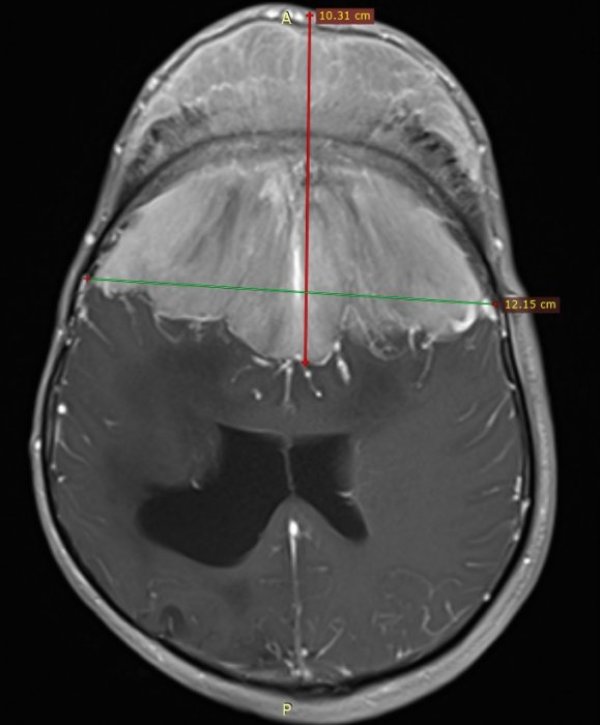

41-годишен мъж с мозъчен тумор над 1 кг е бил спасен след високорискова операция.

Подобни казуси, с толкова голям тумор и с изключително сложна локализация, има само няколко в света. Избират нов подход, като се надяват това значително да ограничи кръвозагубата. Първоначално извършват селективно запушване на голяма част от хранещите съдове на тумора, под високотехнологичен рентгенов и термографски контрол.